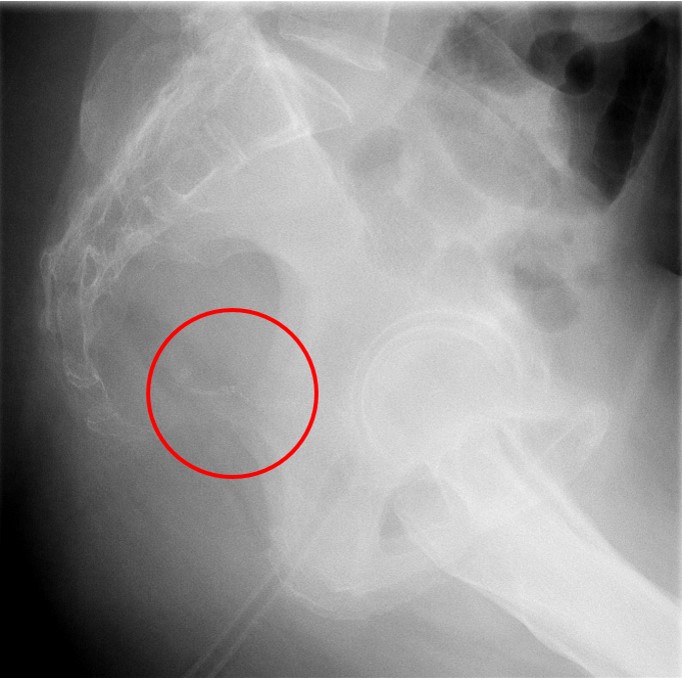

- The technologist will obtain a scout radiograph to include the upper abdomen. Evaluate for the location of the surgical chain sutures

(key image 1).

- There are usually two "sets" of surgical chain sutures.

- The first is located in the epigastric area at the level of the gastrojejunal anastomosis.

- The second is usually located in the left midabdomen. This is the site of the jejunojejunal anastomosis.